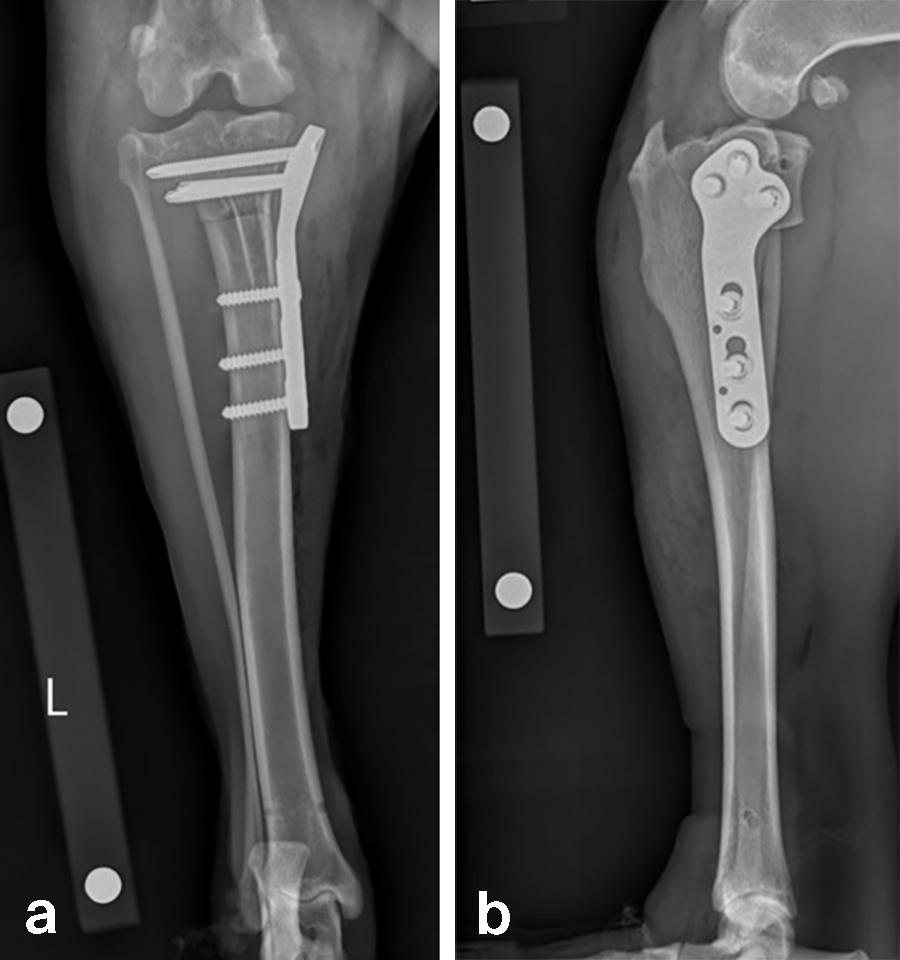

A 23.3 kg 3-year-old spayed female black Labrador Retriever presented with a history of chronic, progressive left pelvic limb lameness. Her clinical examination was suggestive of left cranial cruciate ligament (CCL) rupture. Medical and surgical treatment options were discussed with the clients. They elected to have Rosie’s knee treated with arthroscopy and TPLO.

Left stifle arthroscopy was performed and a partial CCL rupture with incompetent remand was identified. The remaining CCL was debrided with a motorized shaver. The meniscus was healthy/non-injured based on visual inspection and probing. Arthroscopy portals were closed, and exposure of the proximomedial tibia was performed.

Based on preoperative templating, a 21 mm radial saw blade was used to perform an osteotomy of the proximal tibia. The plateau was leveled to a final target slope of 5° and the osteotomy was stabilized with a 3.5 mm ARC TPLO plate.

In Rosie’s case, the plate fit was excellent and the TPLO was performed without complication. Postoperative radiographs illustrate excellent plate position and screw placement and compression across all aspects of the osteotomy. Rosie recovered uneventfully from surgery and at the time of recheck (7 weeks postoperation) was using the operated limb without visible lameness. The knee examination was unremarkable, and radiographs demonstrated robust healing of the TPLO.